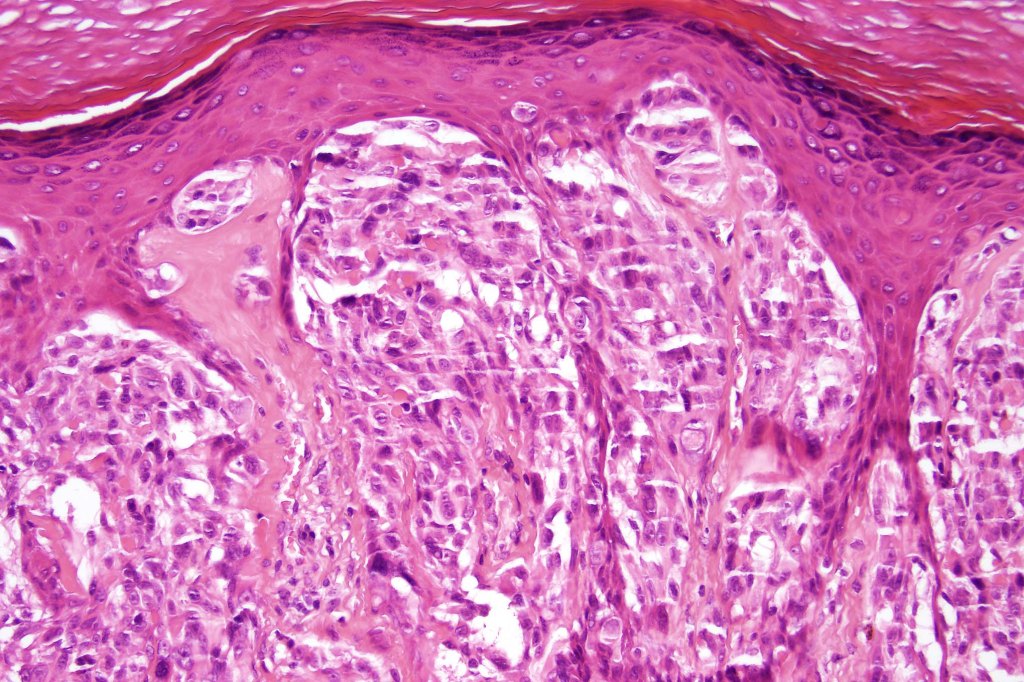

Combined common melanocytic nevus & BAP1-inactivated melanocytoma